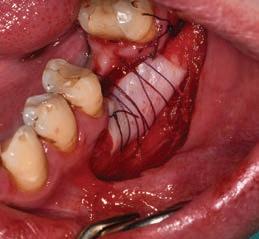

Grafting of soft tissue can be done at three different time periods: before implant placement (Figs 4a-c), at the same time (Figs 5a-c) or after implant placement (Figs 6a-c). Experienced clinicians may opt to perform an EPT simultaneously with implant placement as this saves multiple surgical procedures and is more cost effective. This is shown in Fig 5 and also in the video link provided. This is a complex procedure which should not be attempted by inexperienced clinicians. Grafting before the implant placement is the more predictable procedure and provides a better implant environment to place the implant.

Figure 4a: Pre-operative view showing alveolar mucosa almost to crest of ridge Figure 4b: Graft secured with vestibular deepening done as well Figure 4c: Post-operative view showing graft healing after 8 weeks

Figure 5a: Preoperative view with mucogingival line shown in blue Figure 5b: Simultaneous implant placement and epithelial palatal transplant Figure 5c: Postoperative view with crowns placed. Rugae can be seen but, as it is not an aesthetic area, this is of no consequence Figure 6a: Implants placed years before with peri-implantitis and no keratinized attached tissue buccal of implants. Figure 6b: Graft providing keratinized tissue as well as vestibuloplasty. Patient can wear prosthesis but it has to be eased to ensure no pressure on graft Figure 6c: Postoperative view showing a stable attached peri-implant keratinized tissue and vestibular deepening giving better access for plaque control